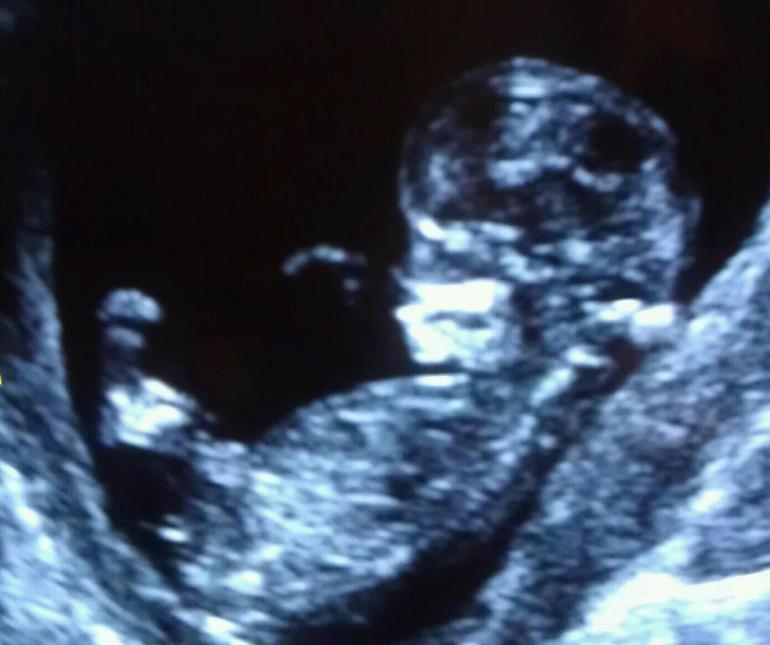

Если первый врач определял по уголу наклона полового бугорка (у мальчиков более 30 градусов угол со спинкой, у девочек параллельно позвоночнику), то могла случиться ошибка, вот фото узи с сайта ingender, все это девочки...

Мне в 13 недель врач кулаком в грудь бил и говорил что мальчик будет. Как видите.